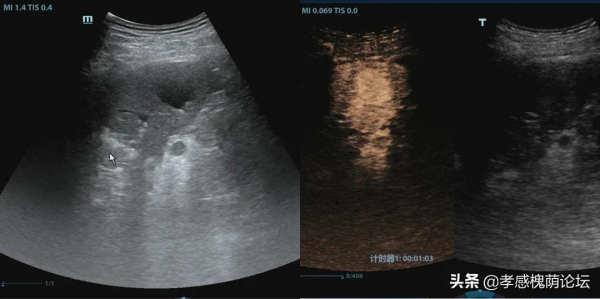

程先生因高空墜落急診入院,首次檢查除腦部受傷、骨折外,無其它外傷。三日後複查超聲檢查時,發現脾臟內可見二個“水泡”,這是什麼?出血?破裂?這讓臨床醫生猶豫不決,關鍵時刻,想到了超聲影像科有一門獨門絕技--超聲造影技術。徵得患者及其家屬同意後,超聲影像科醫生使用超聲超聲造影技術僅用4分鐘快速做出了診斷——外傷導致了脾臟內假性動脈瘤形成(備註:假性動脈瘤是外傷後脾臟內小動脈破裂形成的類似於腫塊樣的東東)。

超聲造影就是在常規超聲檢查的基礎上,透過外周靜脈注射超聲造影劑(又被稱為超聲增強顯影劑),實時動態地觀察組織的微血管灌注資訊,以提高病變的檢出率並對病變的良惡性進行鑑別。整個檢查過程相當短暫,約5-10分鐘左右即可完成,是一項無創、無電離輻射的新型影像學技術。超聲造影相當於對腫塊進行“塗色”,不僅可以讓腫塊更加顯而易見,小腫塊無處遁形,我們還可以根據腫塊“塗色”的速度和具體方式來看清腫塊的本質,判斷是“好人”還是”壞人”。

超聲造影技術在外傷診斷中是在二維超聲及彩色多普勒超聲的基礎上,利用超聲造影劑更加清晰、動態地觀察組織的病變特點,該技術可對出血點進行強化,對外傷導致的肝、脾等臟器破裂敏感性極高,可以透過動態反映臟器的血流灌注特徵和增強損傷區與周圍正常組織的差別,提高超聲診斷臟器破裂的準確性。